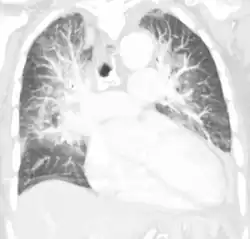

| Pulmonary edema with small pleural effusions on both sides | |

Chest X-ray has been used for many years to diagnose pulmonary edema due to its wide availability and relatively cheap cost.[4] A chest X-ray will show fluid in the alveolar walls, Kerley B lines, increased vascular shadowing in a classical batwing peri-hilum pattern, upper lobe diversion (biased blood flow to the superior parts instead of inferior parts of the lung), and possibly pleural effusions. In contrast, patchy alveolar infiltrates are more typically associated with noncardiogenic edema.[3]